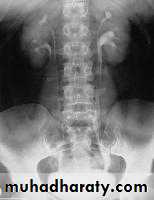

Diagnosis : U/S or IVU,CT scan: absent kidney on that side + compensatory hypertrophy of the contralateral kidney

Diagnosis ultrasound, IVU, CT scan

U/S, IVU, CT scan, MRI